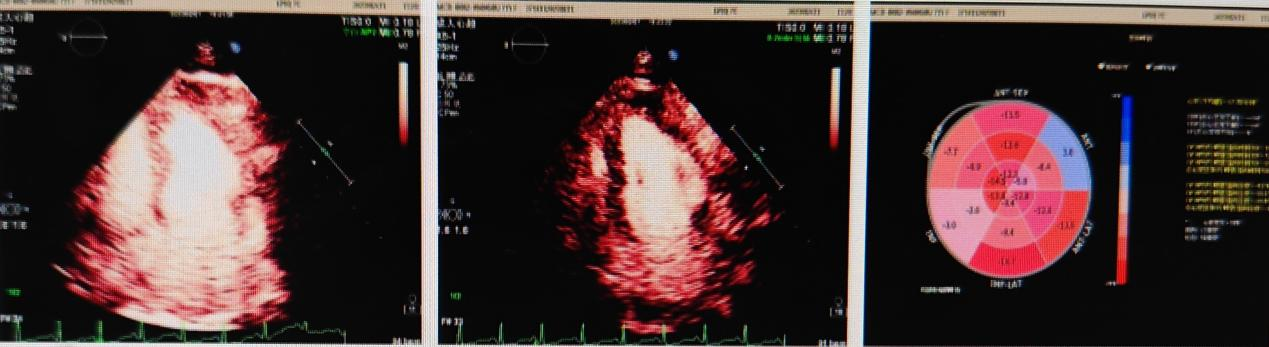

检查伊始,医用超声研究室韩东刚副主任医师和患者友好互动,以缓解患者的紧张情绪。开始检查后,在完成心肌应变评估的基础上,开始心肌超声造影(MCE)检查,静息状态下缓慢推注超声造影剂(SONOVUE)1次1.0ml,13秒右心显影,15秒左心显影。静息态造影显示,患者室壁运动及心肌灌注均正常。随后行药物负荷状态下MCE,负荷态心肌灌注分析显示:注射瑞加诺生后1-3分钟,峰值期(心率最高96次/分)室间隔基底段、中段、左室心尖部及左室侧壁心肌灌注稍差,约30-60秒后恢复,未见持续充盈。4分钟后,心率逐渐降至80次/分以下,声学造影灌注良好,多次爆破后未见明显充盈缺损及延迟征象。